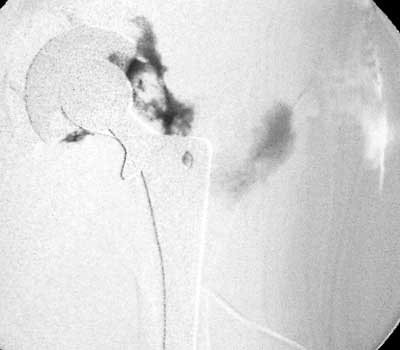

Dry tap secondary to large greater trochanteric bursa, 20

gauge spinal needle placed in bursa under fluoroscopic guidance

Scar with focal area of drainage. Dry tap secondary to large greater trochanteric bursa with

sinus tract draining to skin

Dry tap secondary to sinus tract decompression

Sinus tract draining posteriorly